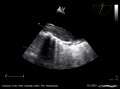

An echocardiogram displaying the true lumen and false lumen of an aortic dissection: In the image to the left, the intimal flap can be seen separating the two lumens. In the image to the right, color flow during ventricular systole suggests that the upper lumen is the true lumen.

The transesophageal echocardiogram (TEE) is a relatively good test in the diagnosis of aortic dissection, with a sensitivity up to 98% and a specificity up to 97%. It has become the preferred imaging modality for suspected aortic dissection. It is a relatively noninvasive test, requiring the individual to swallow the echocardiography probe. It is especially good in the evaluation of AI in the setting of ascending aortic dissection, and to determine whether the ostia (origins) of the coronary arteries are involved. While many institutions give sedation during transesophageal echocardiography for added patient comfort, it can be performed in cooperative individuals without the use of sedation. Disadvantages of TEE include the inability to visualize the distal ascending aorta (the beginning of the aortic arch), and the descending abdominal aorta that lies below the stomach. A TEE may be technically difficult to perform in individuals with esophageal strictures or varices.